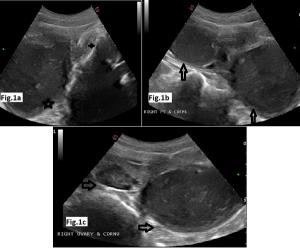

An 18-year-old boy with complaints of swelling in floor of mouth since childhood and difficulty with movement of tongue. On physical examination, sublingual large swelling was noted. Overlying surface was reddish, however no signs for active inflammation seen. Ultrasound, contrast enhanced CT scan and MRI were done.